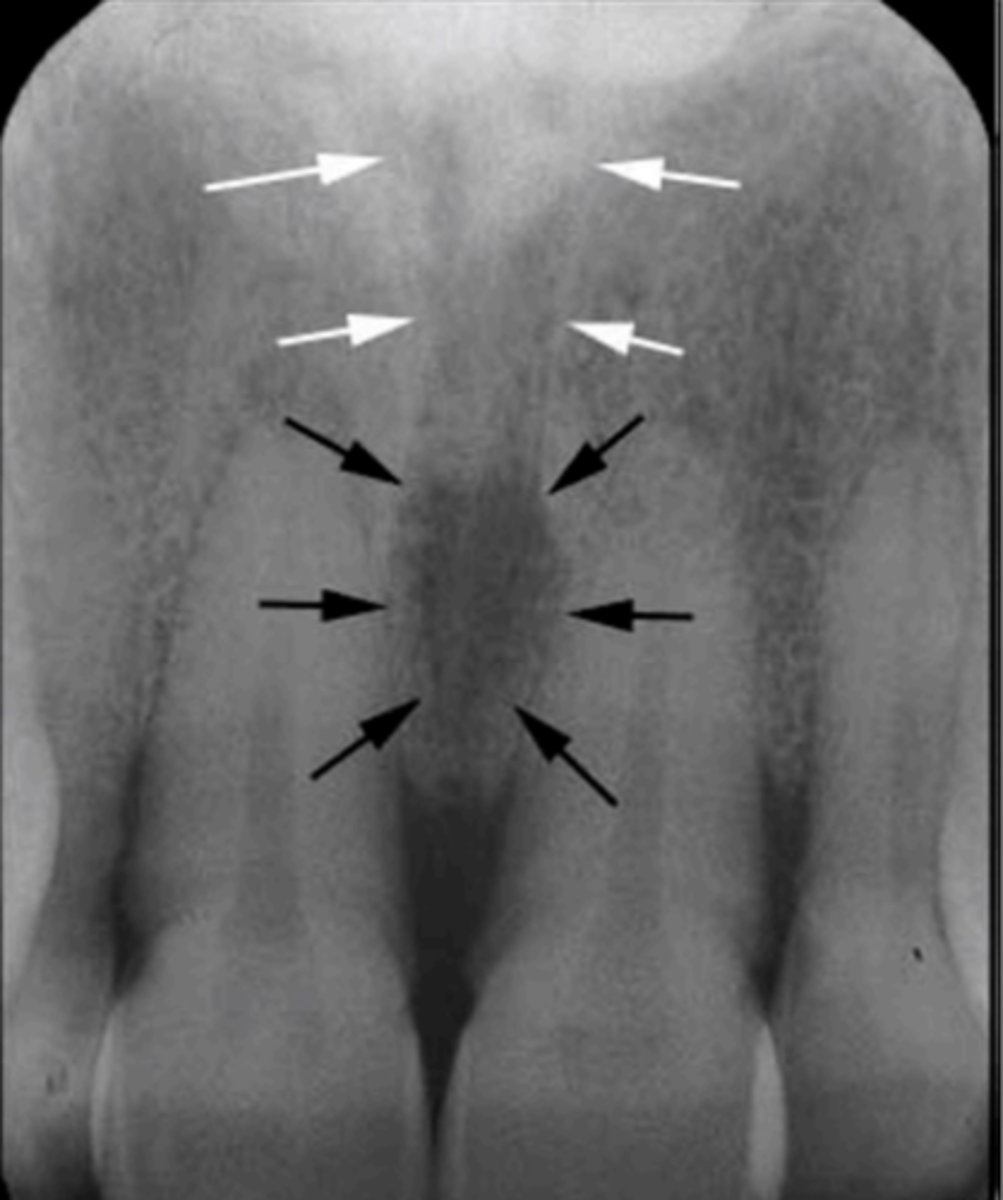

White arrow- nasal conchae

Identify both structures

Identify the round, ovoid radiolucent structure indicated by the black arrows.

<p>Identify the round, ovoid radiolucent structure indicated by the black arrows.</p>

Identify the straight, radiopaque lines indicated by the white arrows.

<p>Identify the straight, radiopaque lines indicated by the white arrows.</p>